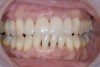

The pretreatment situation.

Figure 1

The clinical application of this protocol is illustrated in a patient situation where laminate veneers were placed on four maxillary incisors to replace lost tooth structure and restore function and esthetics. The failing restorations were removed, followed by a conservative veneer preparation (Figure 1 and Figure 2). The bonding surfaces of the feldspathic porcelain veneers were acid-etched with hydrofluoric acid for 2 minutes (Figure 3) and thoroughly rinsed. Then a silane coupling agent was applied (Figure 4). Figure 5 demonstrates the situation after bonding the veneers to the teeth with a composite resin luting agent.